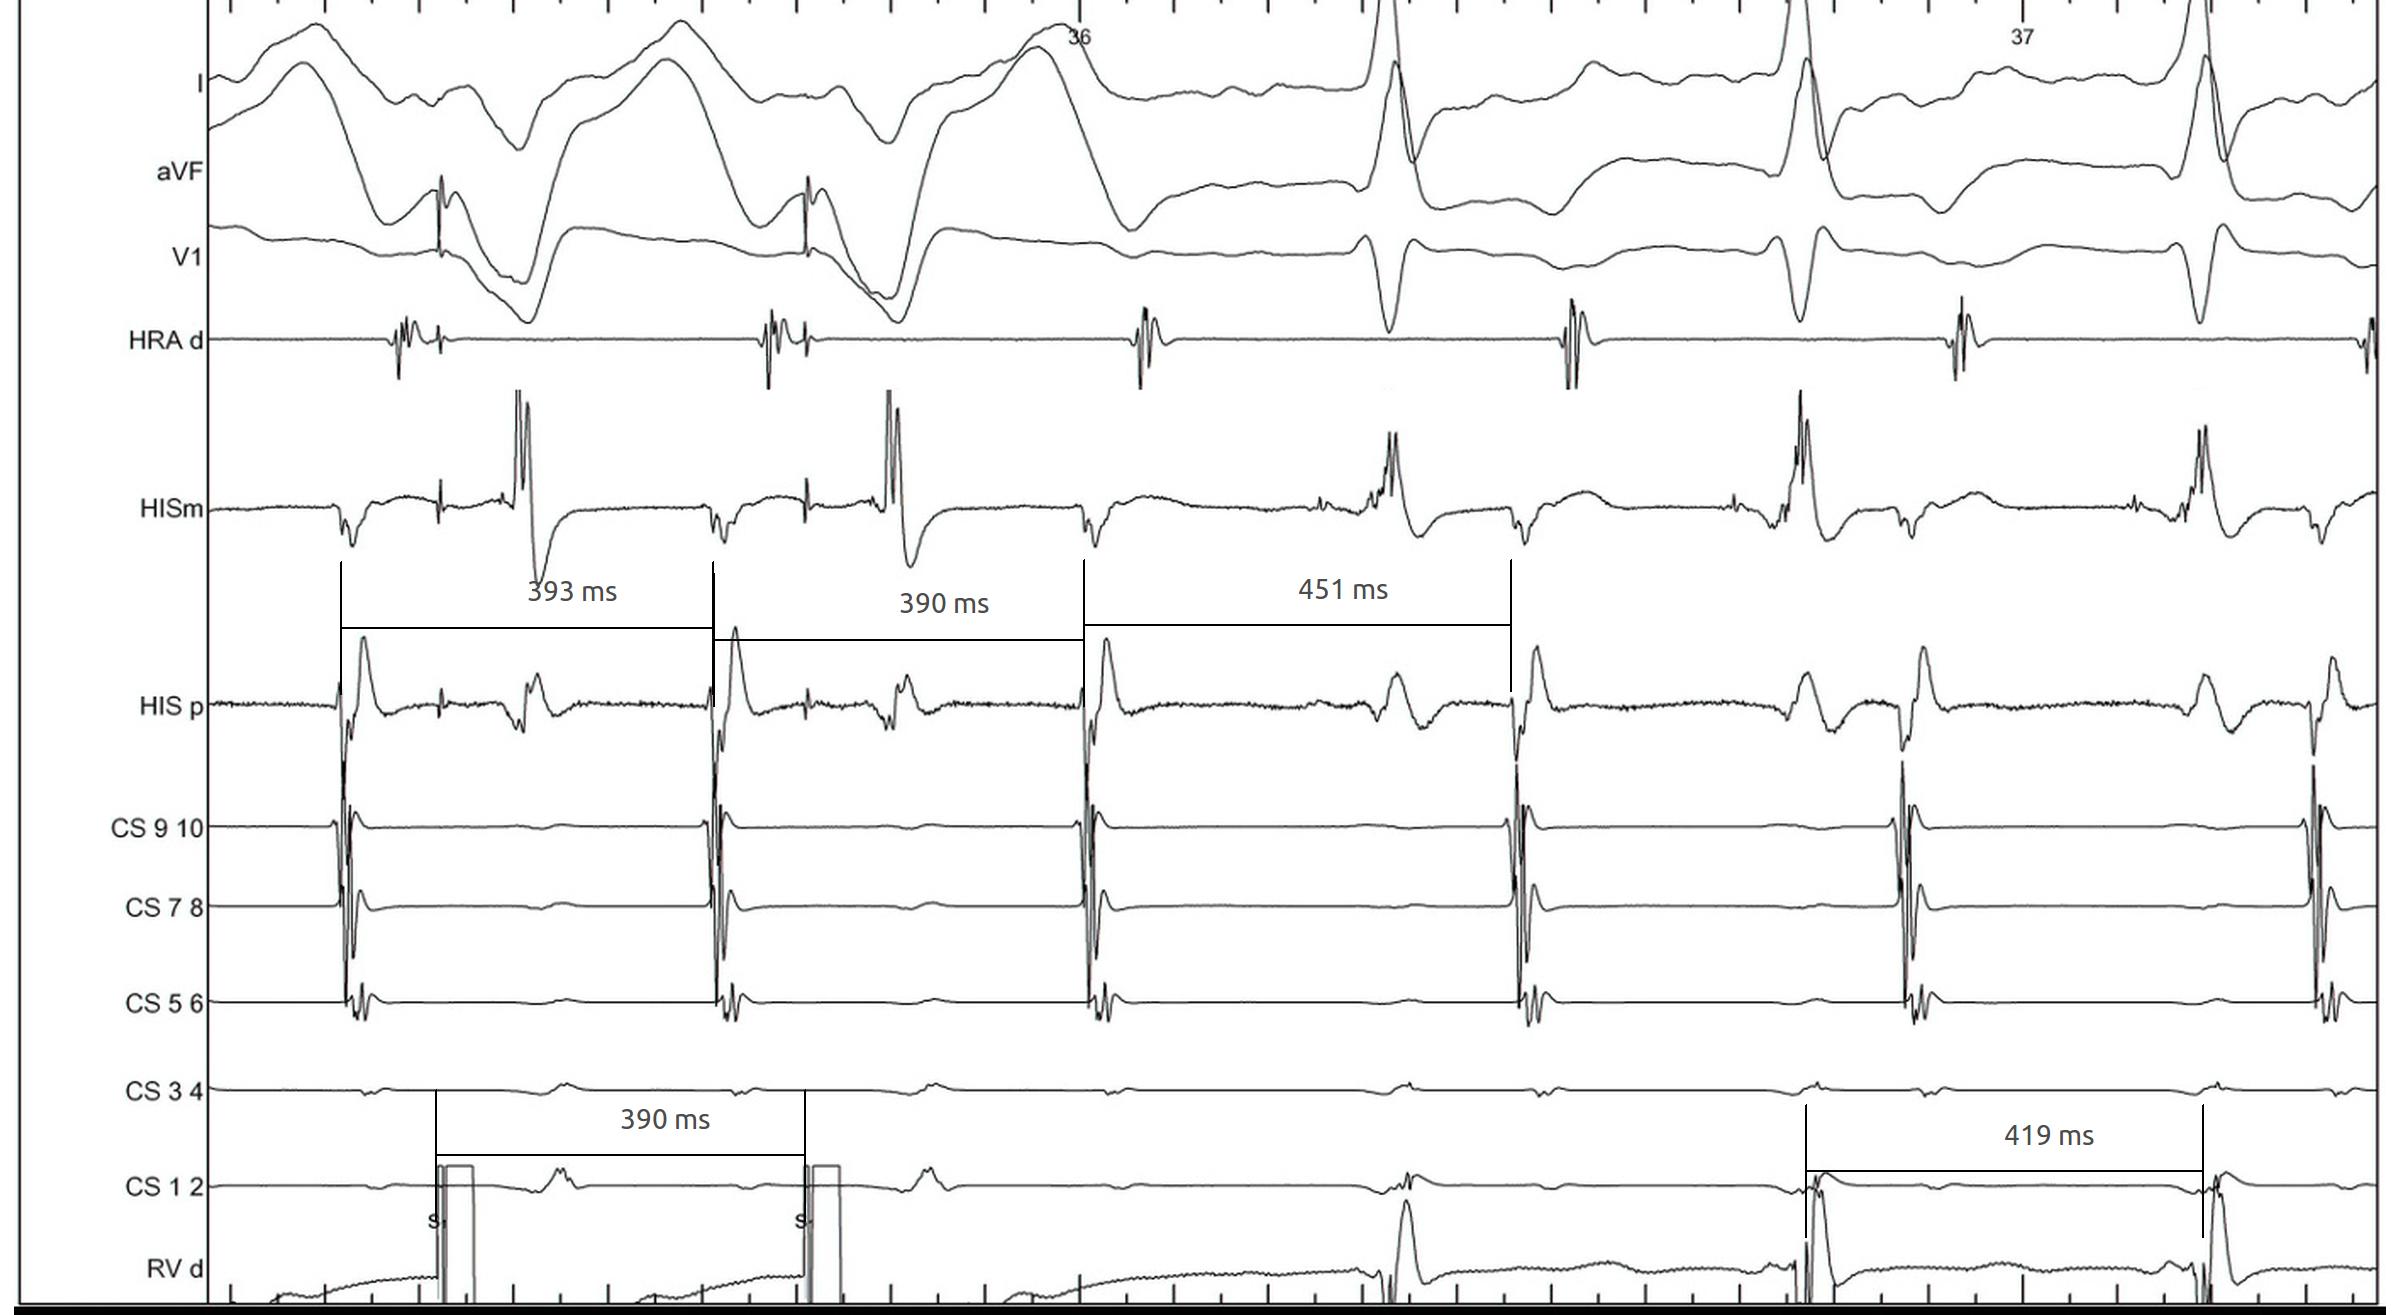

Differential pacing

• VA interval during pacing from apex and base

• Shorter from apex for nodal conduction

• Shorter from base for AP conduction

RV apex pacing

rv_apex_va.jpg

RV base pacing

rv_base_va.jpg